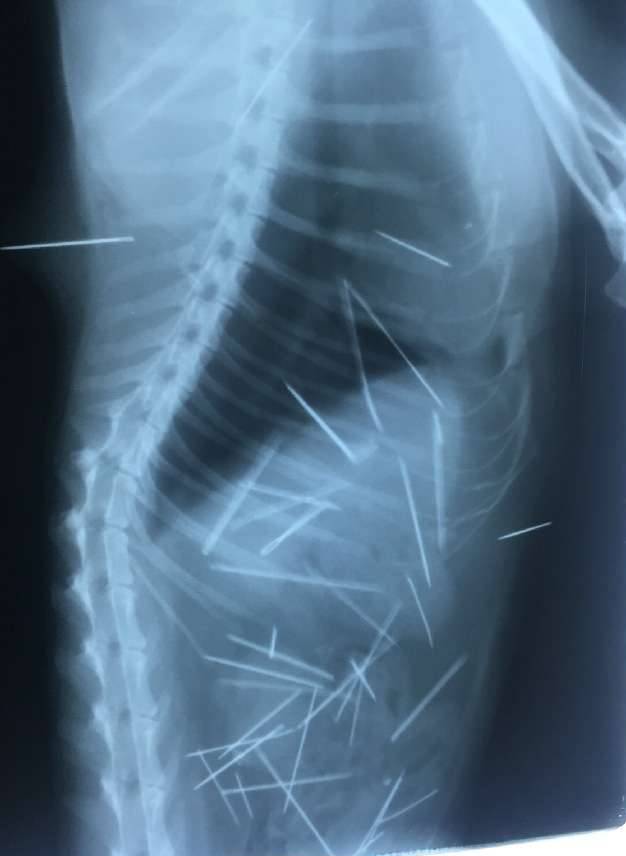

▼这次动物医院连续照了53次X光片,发现猫咪体内有多根细针,有些已经生鏽。

▼其中7根针在皮肤和肌肉、3根针和2根断针在胸腔心脏旁边,30根针在腹腔,其中有4根是插入到左侧肾脏。

▼现在这些针已经开始游离,猫咪很痛苦。医生表示手术也只能取出2/3。

从X光片可以看到,猫咪体内布满密密麻麻的细针,看起来怵目惊心。一年多来,猫咪一直忍受针刺的痛苦,牠无法说话,只能默默承受。在热心人士的帮忙协助下,猫咪终于做完手术,希望牠能够快点好起来,不要再遭遇这样可怕的事。分享出去,让大家都看到吧。